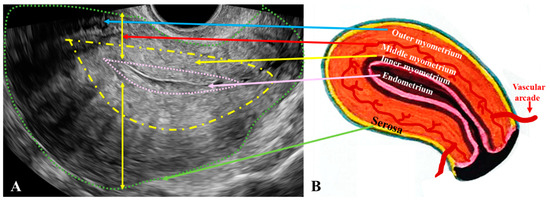

Background/Objectives: Adenomyosis (A) is a benign but invasive uterine condition frequently associated with structural changes in the uterine wall that may contribute to infertility. Methods: This is a retrospective study involving 140 patients: 100 diagnosed with primary infertility (PI) or secondary infertility (SI) and 40 in the control group. All patients were assessed using transvaginal two-dimensional, three-dimensional, and hysterosalpingo-contrast sonography (HyCoSy), performed in the early proliferative phase. Evaluated parameters included uterine dimensions, endometrial thickness, and characteristics of the junctional zone (JZ). Criteria such as JZmax > 5 mm or JZmax − JZmin > 5 mm, alongside other findings, supported the diagnosis of adenomyosis. Results: Patients with PI showed larger uterine longitudinal diameters, while SI patients had thicker JZ measurements. PI patients were significantly younger. Histopathological examination confirmed the presence of endometrial glands and periglandular stroma disrupting myometrial architecture, forming chronic lesions potentially linked to infertility. Conclusions: HyCoSy revealed variable depths of myometrial invasion by A, with some cases extending near the serosa. The chronic lesions found in histopathological examination were potentially linked to infertility. Full article